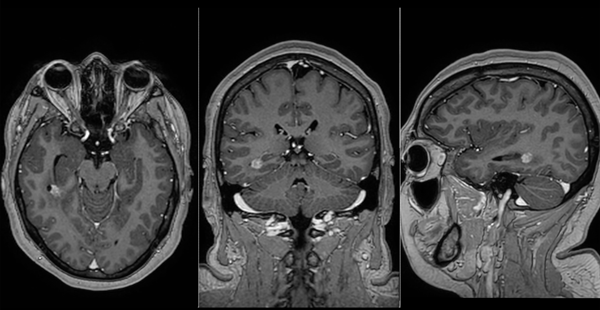

Descripción del caso: paciente femenina de 28 años, sin antecedentes médicos de relevancia, que consulta por crisis de ausencia, cefalea holocraneana, náuseas y vómitos con tres años de evolución. La resonancia magnética con espectroscopia reveló una lesión en el lóbulo temporal derecho, caracterizada por un aumento del pico de colina y una disminución del N-acetilaspartato, hallazgos compatibles preliminarmente como lesión tumoral primaria. El electroencefalograma mostró lentificación de la actividad de fondo en la región centrotemporal derecha. Ante este conjunto de hallazgos clínicos, radiológicos y electrofisiológicos, se decidió realizar una cirugía con criterio oncológico, priorizando este abordaje por sobre el enfoque exclusivamente epileptégeno.

Case description: a 28-year-old female patient with no significant medical history presented with absence seizures, holocranial headache, nausea, and vomiting of three years' duration. Magnetic resonance imaging with spectroscopy revealed a lesion in the right temporal lobe characterized by an increased choline peak and a decreased N-acetyl aspartate level, findings preliminarily consistent with a primary tumor. The electroencephalogram showed slow background activity in the right centrotemporal region. Given this combination of clinical, radiological, and electrophysiological findings, it was decided to perform oncological surgery, prioritizing this approach over a purely epileptogenic approach.

Los autores presentan el caso de una paciente con una lesión temporal derecha evidenciada en resonancia magnética y posteriormente confirmada como lesión glial mediante estudio anatomopatológico, cuya manifestación clínica inicial fueron crisis epilépticas.

El abordaje terapéutico consistió en la resección microquirúrgica de la lesión tumoral, guiada por estereotaxia para acceder de manera precisa a un tumor pequeño y profundo. Coincido en que, cuando las crisis epilépticas tienen origen en una patología tumoral, debe priorizarse el tratamiento de la lesión sobre el control aislado de las crisis. En este caso, el foco epileptógeno (documentado en EEG) coincidía con la localización de la lesión, lo que simplificó la estrategia quirúrgica. La resección máxima y segura constituye no solo el principal factor pronóstico de sobrevida, sino también el determinante más relevante para lograr el control de las crisis.

El video presentado es claro, con excelente calidad de imagen, y expone de manera ordenada la relación de la lesión con estructuras superficiales y profundas, seguido de los detalles técnicos de la resección. Se observa, sin embargo, una discrepancia: durante el video se menciona un posible remanente tumoral, mientras que la resonancia posquirúrgica sugiere resección completa. En estos casos, resulta aconsejable realizar neuroimágenes de seguimiento a menor intervalo para confirmar la resección total y descartar la necesidad de terapias complementarias, considerando que se trataba de una lesión grado I según la OMS.